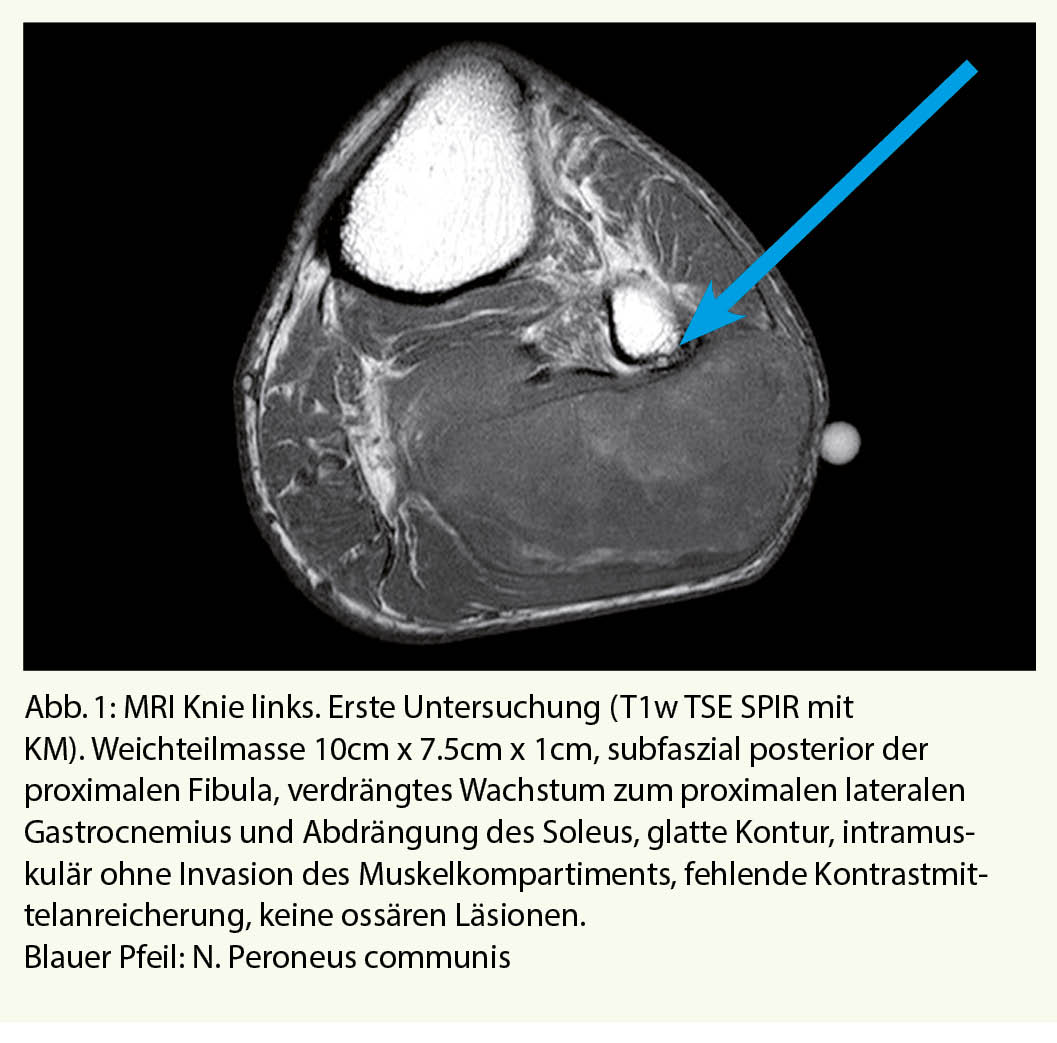

Klinisch zeigte sich eine glatte, rundliche, nicht druckdolente tumoröse Struktur im proximalen, posterioren Unterschenkel sowie eine Fussheberparese der ipsilateralen Seite. Die restliche klinische Untersuchung blieb bland. Angaben zur persönlichen Anamnese im Kasten. In der MRT-Untersuchung des linken Unterschenkels zeigte sich eine Raumforderung im postero-lateralen Muskelkompartiment in unmittelbarer Nachbarschaft zum N. peroneus (Abb. 1). Eine invasive Abklärung in Form von Biopsien hat der Patient abgelehnt. Zu den weiteren Nachkontrollen beim Hausarzt kam der Patient nicht mehr.

Mehr als 2 Jahre später erfolgte die erneute Vorstellung beim Hausarzt wegen der nun deutlich zunehmenden Schwellung am Unterschenkel. Jetzt konnte der Patient aufgrund der Schwellung nicht mehr die Hose anziehen. Gewichtsabnahme oder Nachtschweiss wurden verneint. Es wurde eine erneute MRT Untersuchung des Unterschenkels veranlasst (Abb. 2).

In unserem Fall hatte der Tumor bereits bei der ersten MRI Untersuchung eine Grösse > 5cm und eine Lage unmittelbar unterhalb der Muskelfaszien. Ausserdem konnte ein Wachstum dokumentiert werden. Aufgrund dieser Faktoren war eine Abklärung der Dignität mittels Core Nadel Biopsie (der heutige Standard) indiziert.

• Liposarkome im Frühstadium weisen im CT oder MRI keine typischen Malignitätszeichen auf wie Kontrastmittelanreicherung oder lokale Invasion und könnten als «benigne» missdeutet werden. Die Indikation zur ergänzenden Biopsie soll grosszügig gestellt werden.